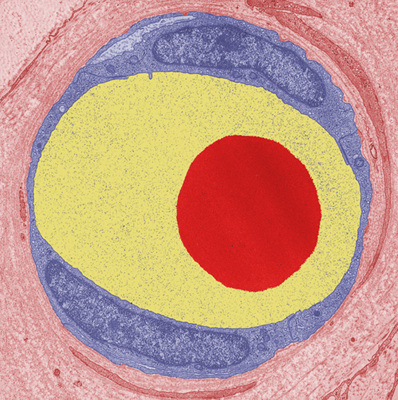

¹®¾îó·³ »ý±ä ¡®¹®¾î¹ß¼¼Æ÷¡¯

¸ð¼¼Ç÷°üÀ» ³»ºÎ ¾Ð·ÂÀ¸·ÎºÎÅÍ º¸È£ÇÏ´Â ¿ªÇÒ <»çÁø: ¹®¾î¹ß¼¼Æ÷(Àû°¥»ö)°¡ ¸ð¼¼Ç÷°ü(ºÓÀº»ö)ÀÇ ¿©°ú ¸·(³ë¶õ»ö)À» °¨½Î°í ÀÖ´Â Çö¹Ì°æ»çÁø> ¿ì¸® ¸ö¿¡ ÀÖ´Â ¸¹Àº .... ¤ÓÀ̹̳ª ±âÀÚ 2009-11-06